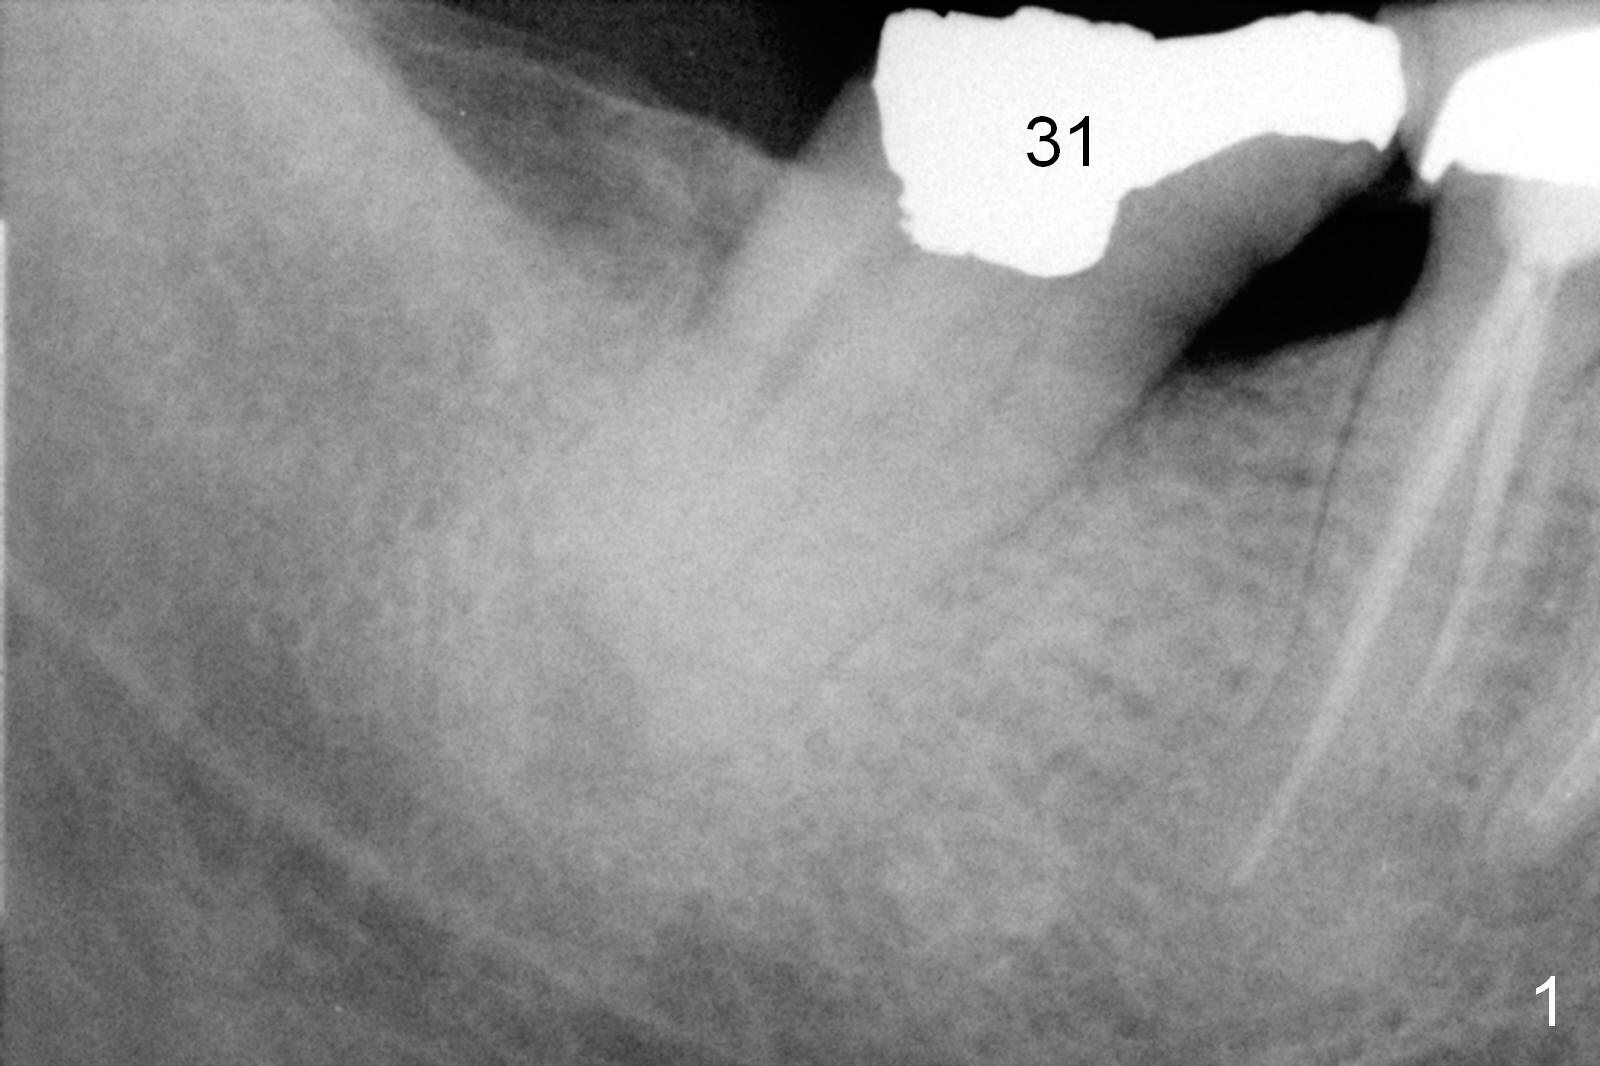

Where to Start Osteotomy? A 45-year-old lady (FY) has mild discomfort at #31 (Fig.31). Periapical radiolucency (Fig.2 arrowheads) is closely associated with the Inferior Alveolar Canal (red dashed line: upper border). Be careful when removing periapical granulation tissue. The socket will be treated with Clindamycin. If there is no severe pain associated with granulation tissue removal, osteotomy can be initiated lingual to the apex. An implant will be placed along the original long axis of the tooth (Fig.3). Otherwise, an implant will be placed in the mesial slope (Fig.4); the implant will be 2 mm longer; the upper end should be in the middle of the socket. Return to